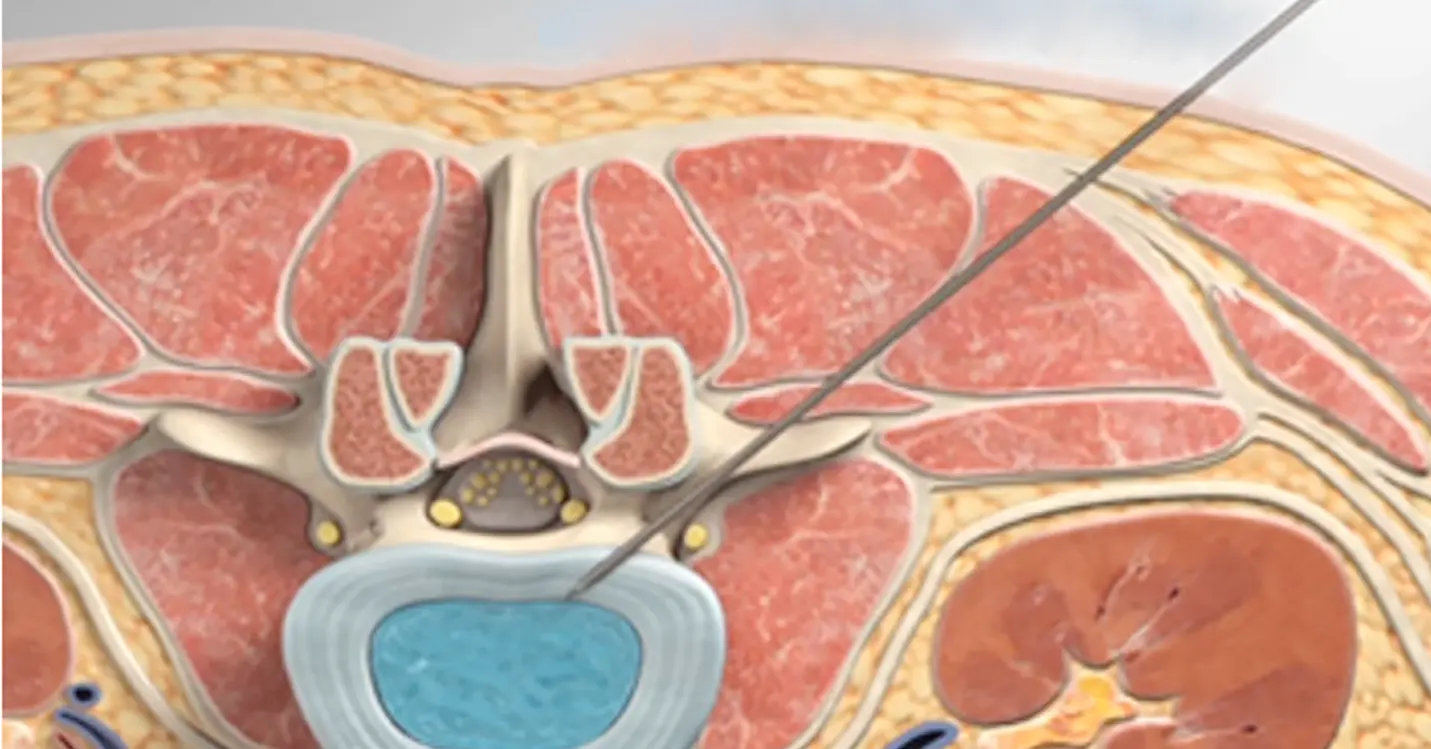

De asemenea, această tehnică ULTRA minim invazivă folosită în operația lombară implică ca mușchii și țesuturile să fie îndepărtate fără a fi secționate printr-o metodă specială care ghidează un dispozitiv printre mușchi până la nivelul discului herniat.

Procesul prin care funcționează acest sistem este fascinant. Totul începe cu planificarea minuțioasă a intervenției, folosind imagistica RMN sau CT pentru a identifica exact locul problemei. Chirurgul inserează apoi dilatatoare progresive, care separă cu delicatețe fibrele musculare, până când se creează un tunel sigur către discul afectat. Odată stabilită această cale de acces, un tub final este plasat pentru a oferi un cadru fix de lucru. Totul este realizat cu ajutorul unui microscop chirurgical, care asigură o vizualizare clară a zonei și o precizie remarcabilă în timpul intervenției.